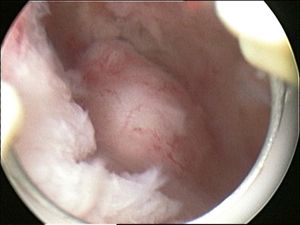

- In a hysteroscopic myomectomy (also called transcervical resection), the fibroid can be removed by either the use of a resectoscope, an endoscopic instrument inserted through the vagina and cervix that can use high-frequency electrical energy to cut tissue, or a similar device.